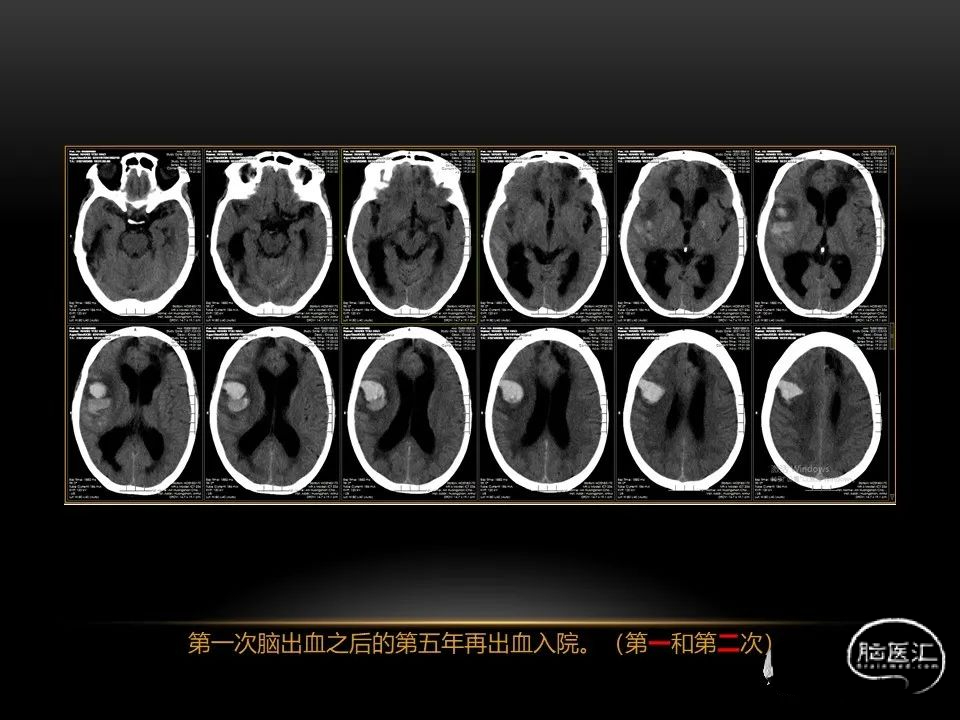

自发性脑出血临床上很常见,不同原因有特征性的出血部位。例如:基底节出血和丘脑出血大多是高血压性脑出血;脑叶出血,特别是多次复发的脑叶出血多见于老年人的脑血管淀粉样变。